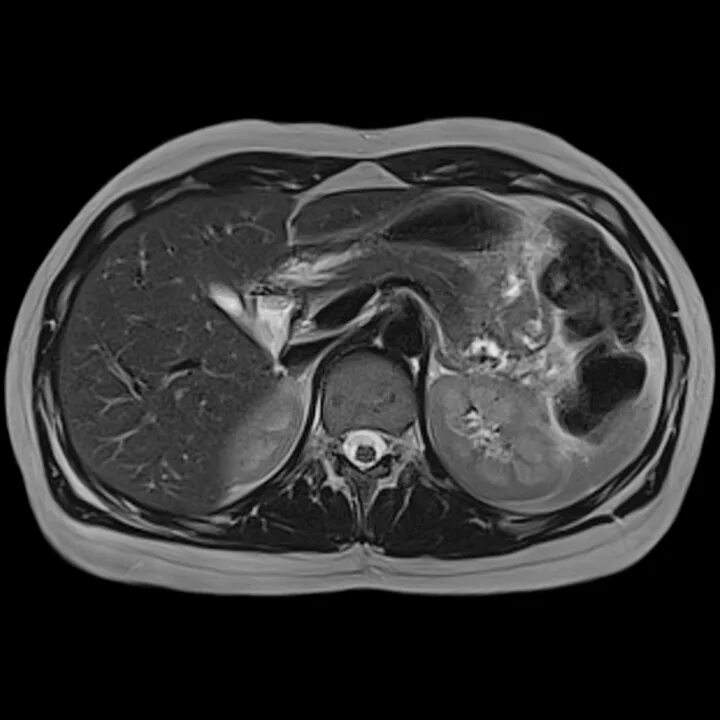

Мрт обп с контрастированием